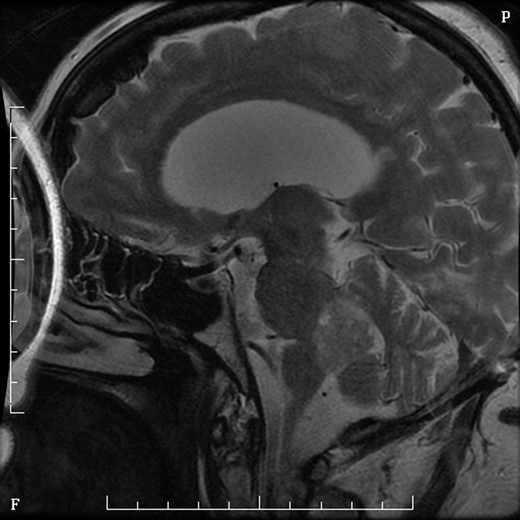

Mrs MM is a 62-year-old female who presented to our institution complaining of a 4-day history of nausea, vomiting and speech difficulties. She initially presented to a peripheral hospital following a fall at home and underwent workup for this. Clinically she scored a Glasgow Coma Scale (GCS) of 14 due to her confusion but had normal strength in all of her limbs. Initial computed tomography brain revealed a 2.6 × 2.5 × 2.1 cm rounded masses enhancing with contrast with areas of calcification in the fourth ventricle and obstructive hydrocephalus (Figs 1 and 2). The following day she underwent magnetic resonance imaging (MRI) brain showed the lesion to be isodense on T1-weighted imaging mildly hypodense on T2-weighted imaging (Fig. 3), and there was no other pathology demonstrated apart from chronic microvascular ischemic changes.

MRI sagittal T2 sequence with gadolinium showing rounded mass in fourth ventricle.